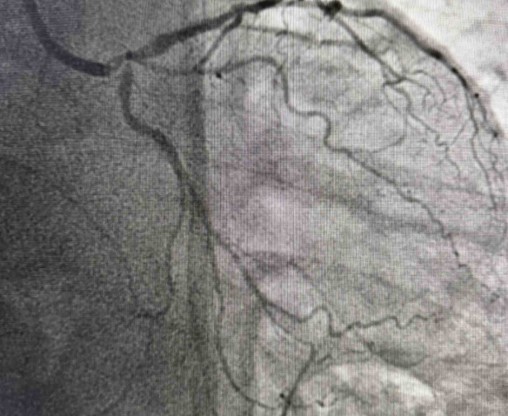

Tokom dva dana u angio sali izvedene su i izuzetno složene intervencije na koronarnim arterijama srca, uključujući perkutane intervencije na hronično - potpuno zapušenim krvnim sudovima srca i intervencije na tzv. glavnom stablu (left main) koja je glavna artrija srca i čije liječenje takođe spada u veoma rizične zahvate u interventnoj kardiologiji.

Složene procedure na koronarnim krvnim sudovima srca izveo je tim ljekara: dr Aleksandar Janjičić, interventni kardiolog, načelnik Odjeljenja za internističke grane Bolnice u Bijeljini, uz asistenciju dr Nenada Božinovića, interventnog kardiologa iz Kliničkog centra u Nišu i stalnog člana evropskog CTO kluba, dr Miloša Trajkovića, kardiologa iz Instituta za kardiovaskularne bolesti Vojvodine i dr Sameda Đedovića, kardiologa, magistra medicinskih nauka, šefa Odjeljenja kardiologije u "Medical Institute Bayer" iz Tuzle.

Kod pacijenta D.B iz Bratunca, koji je prije dvije godine prebolio infarkt i imao hroničnu potpunu zapušenost jedne arterije, urađena je perkutana koronarna intervencija kojom je arterija u potpunosti otvorena. Iako ove procedure imaju niži procenat uspjeha i zahtijevaju veliko iskustvo operatera, uspješno je izvedena. Dan nakon intervencije pacijent dobrog opšteg stanja otpušta se na kućno liječenje.

„Pacijent je imao simptome angine pectoris. Nakon urađene koronarografije verifikovana je teška trosudovna koronarna bolest, gdje su bolesne bile desna koronarna arterija, dok je na lijevoj strani kritično mjesto bilo na glavnom stablu  odakle ide račvanje u dvije grane. Takvi pacijenti uglavnom završavaju na kardiohirurškom konzilijumu i na operaciji bajpasevima. Međutim, odluka konzilijuma u Banjaluci je bila da se, zbog godina života pacijenta,  radi perkutana intervencija na desnoj i lijevoj koronarnoj arteriji uključujući glavno stablo.Takve procedure zahtijevaju da se rade sa kontrolom imidžinga, savremene intravaskularne dijagnostike (IVUS), što smo mi i uradili. To dodatno povećava bezbijednost i preciznost zahvata. Procedura je trajala svega 45 minuta, a pacijent je već narednog dana otpušten kući“, izjavio je dr Janjičić.